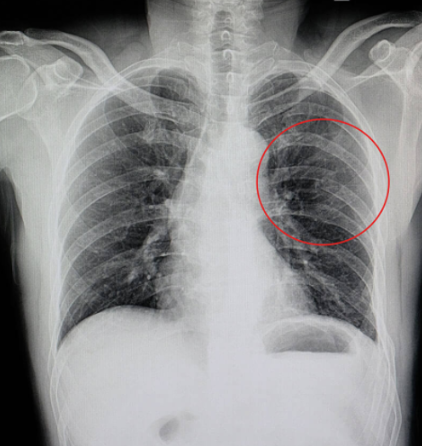

갈비뼈 금간 진단 방법

갈비뼈 금간 여부는 병원에서 다음과 같은 검사를 통해 진단합니다:

- 흉부 X-ray 촬영